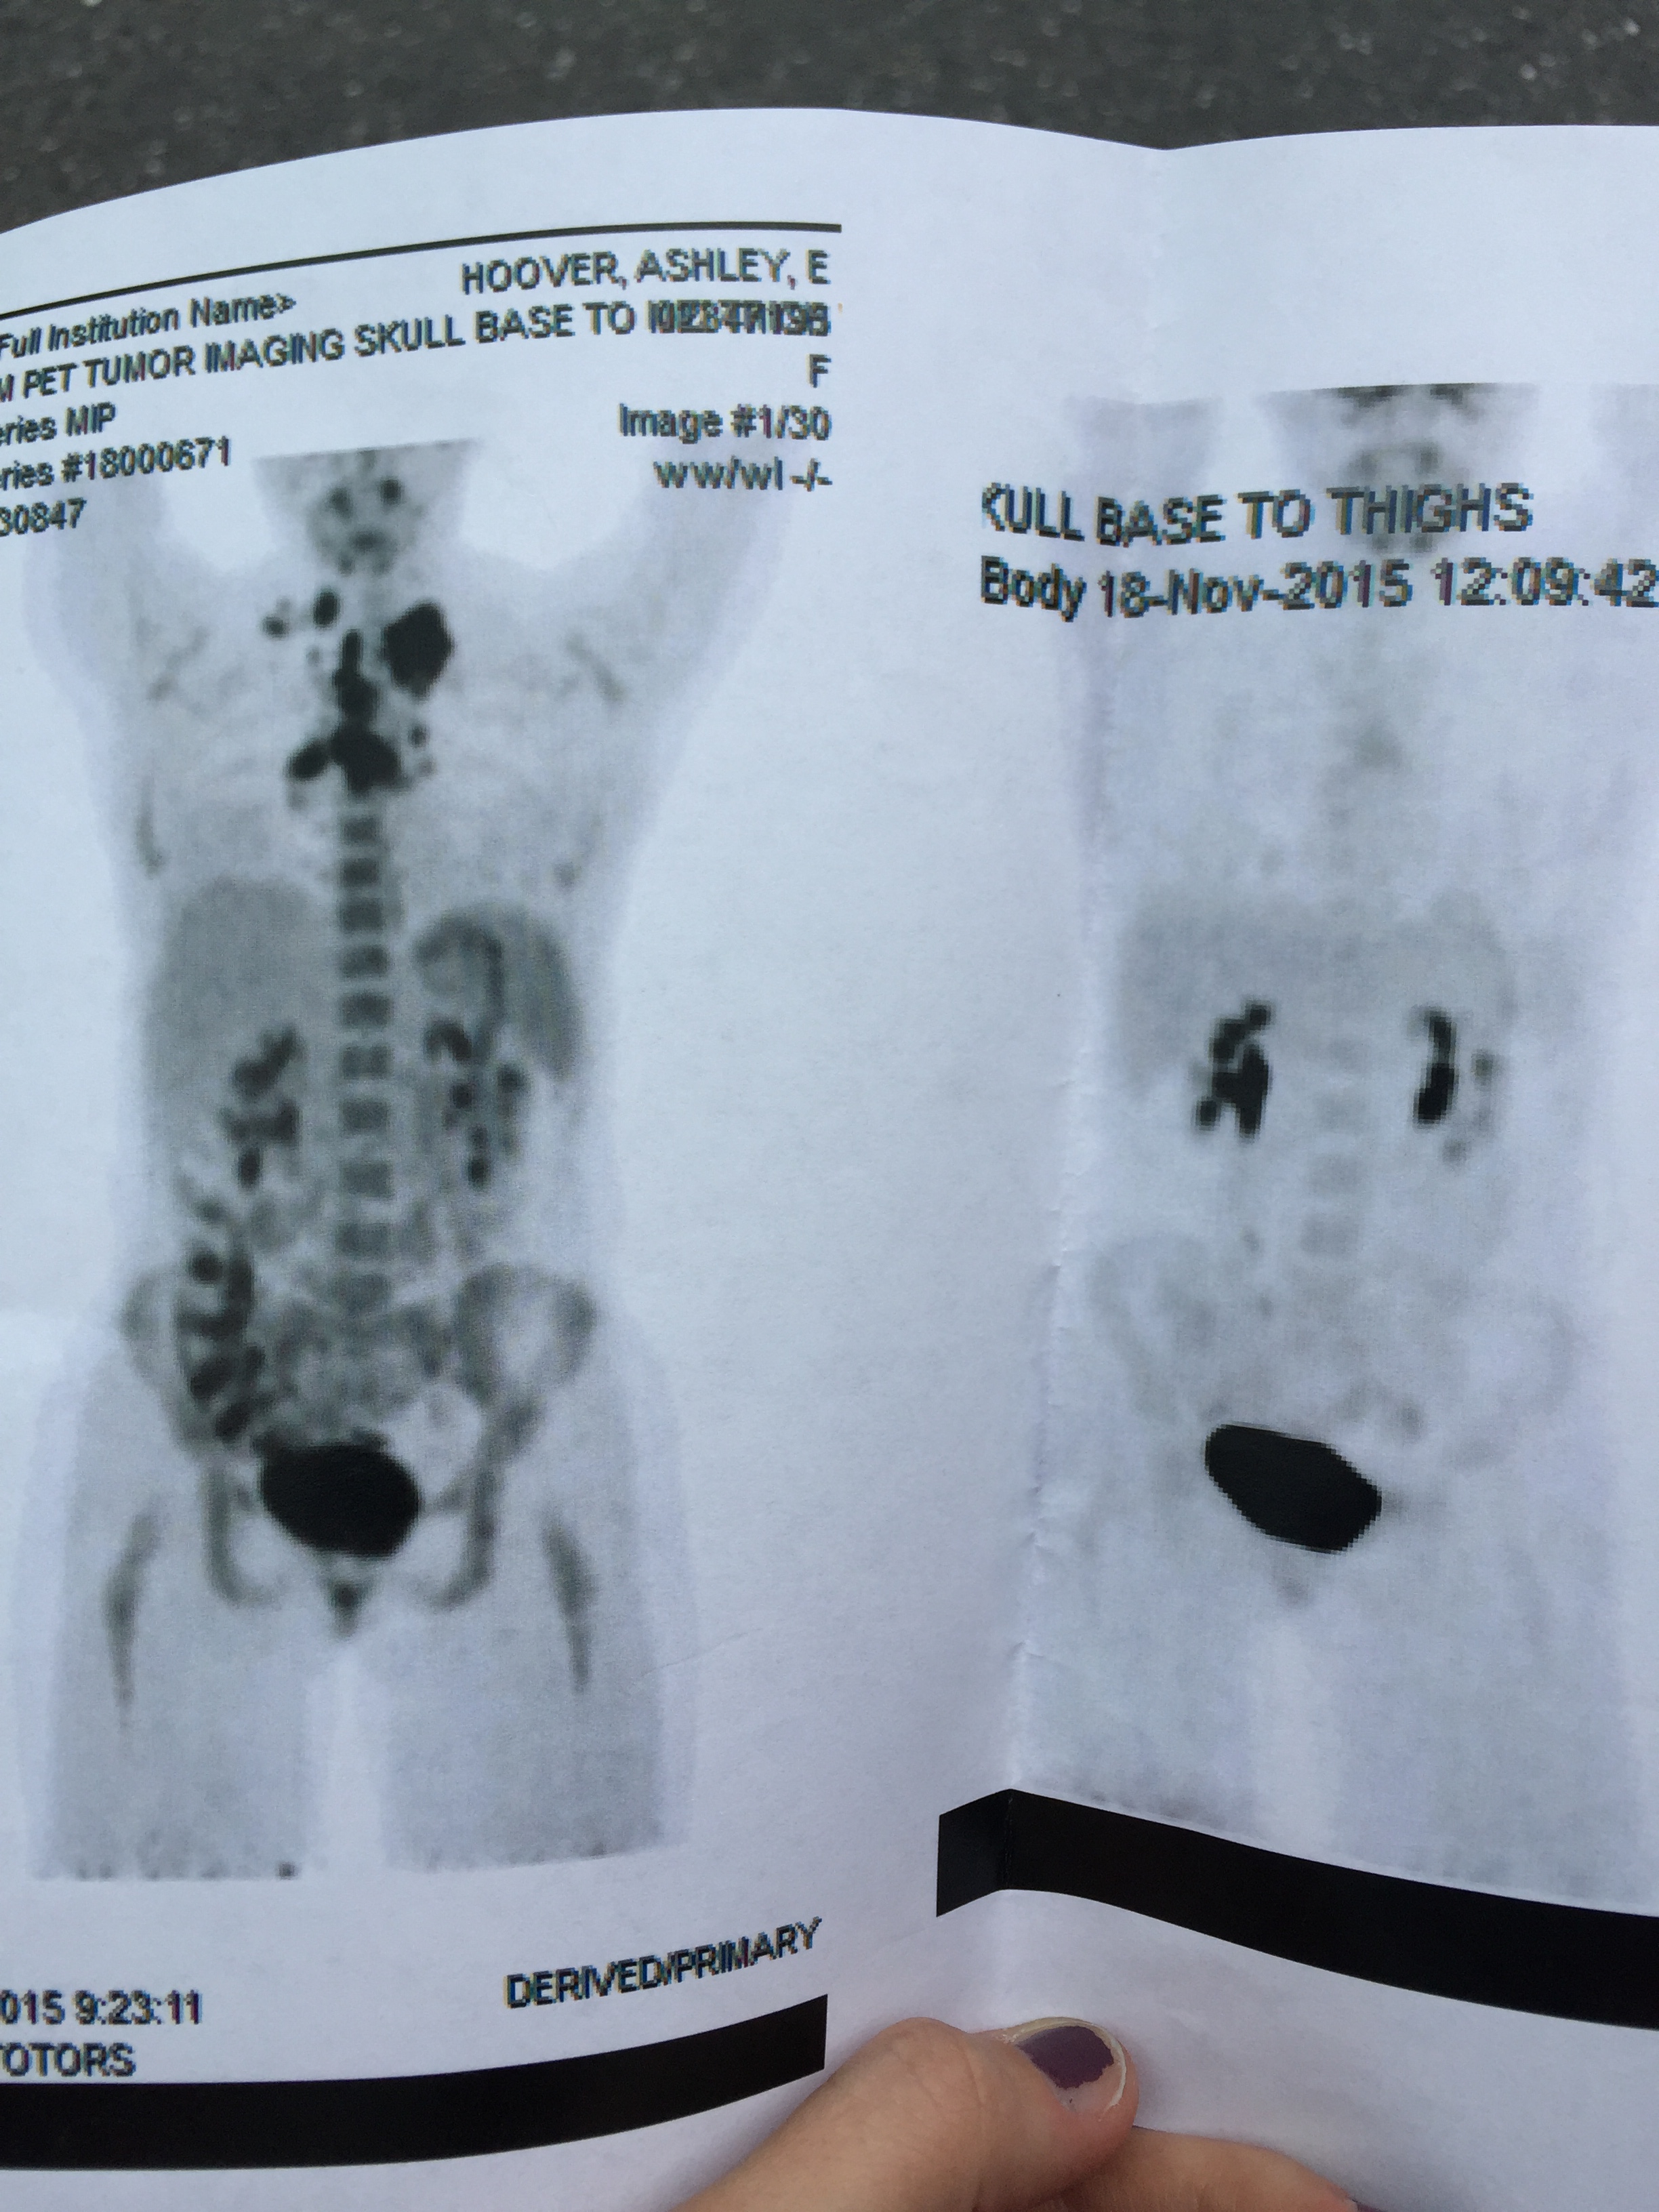

First PET scan and scan 6 months and 12 chemo treatments later